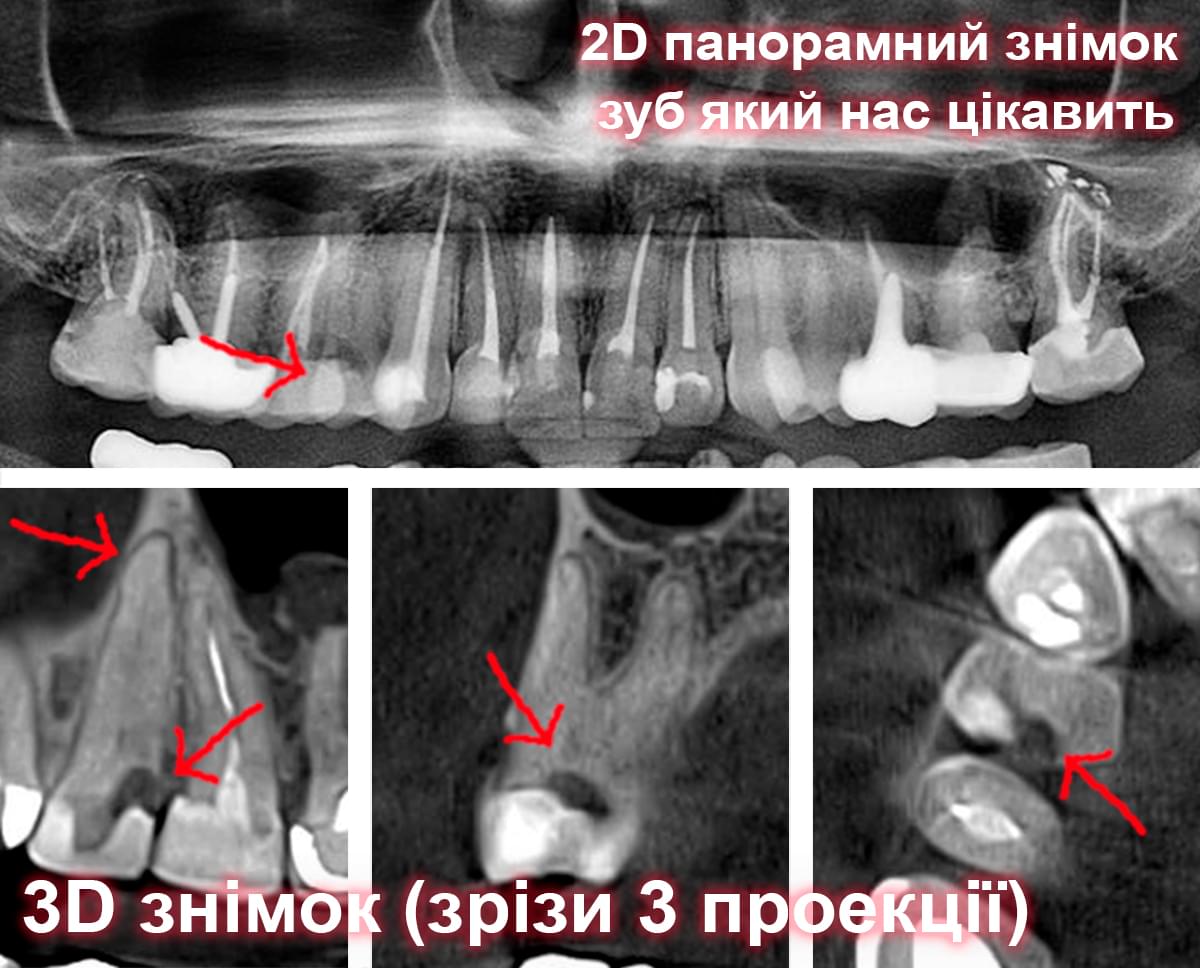

Візуальне порівняння (Кейс одного пацієнта)

Зуб — це не просто монолітний об'єкт, а складна система мікроканалів. На плоскому 2D-знімку вони часто перекривають один одного, створюючи ілюзію простої анатомії.

Непомічений канал — це джерело майбутньої інфекції та причина «загадкового» болю після лікування. Завдяки високій роздільній здатності обладнання MyRay, лікар бачить кожен мікронний канал ще до того, як візьме до рук інструмент.